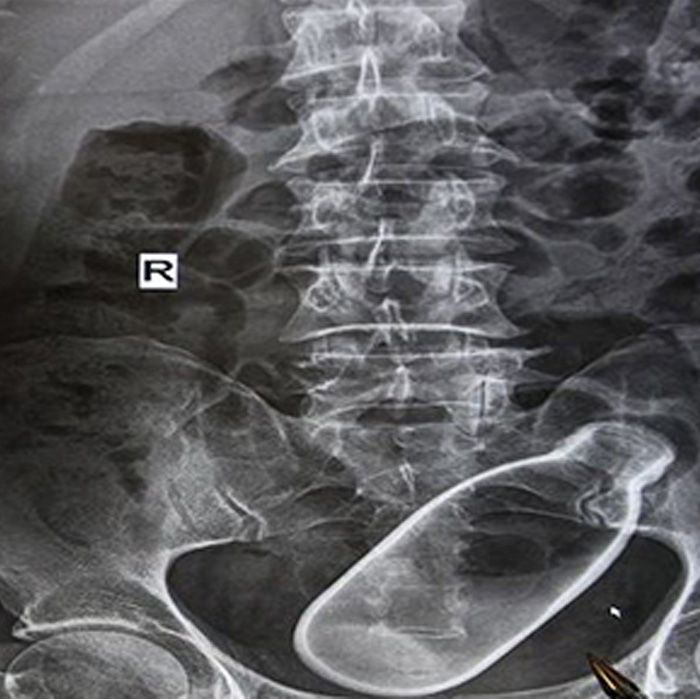

It’s not poisonuse bug spray, but the breakable nature of this milk bottle brings on different nightmares.